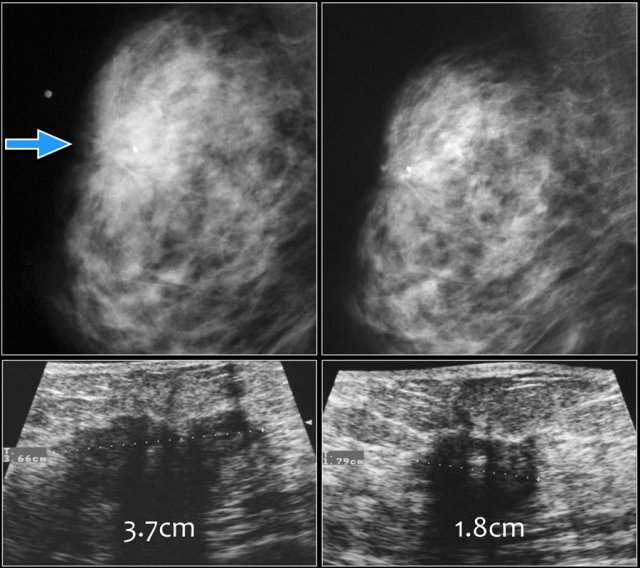

Here images of a biopsy proven malignancy.

On the initial mammogram a marker is placed in the palpable tumor.

Due to the dense fibroglandular tissue the tumor is not well seen.

Ultrasound demonstrated a 37 mm mass with indistinct and angular margins and shadowing.

After chemotherapy the tumor is not visible on the mammogram.

Ultrasound showed shrinkage of the tumor to a 18 mm mass, which was categorized as BI-RADS 6.